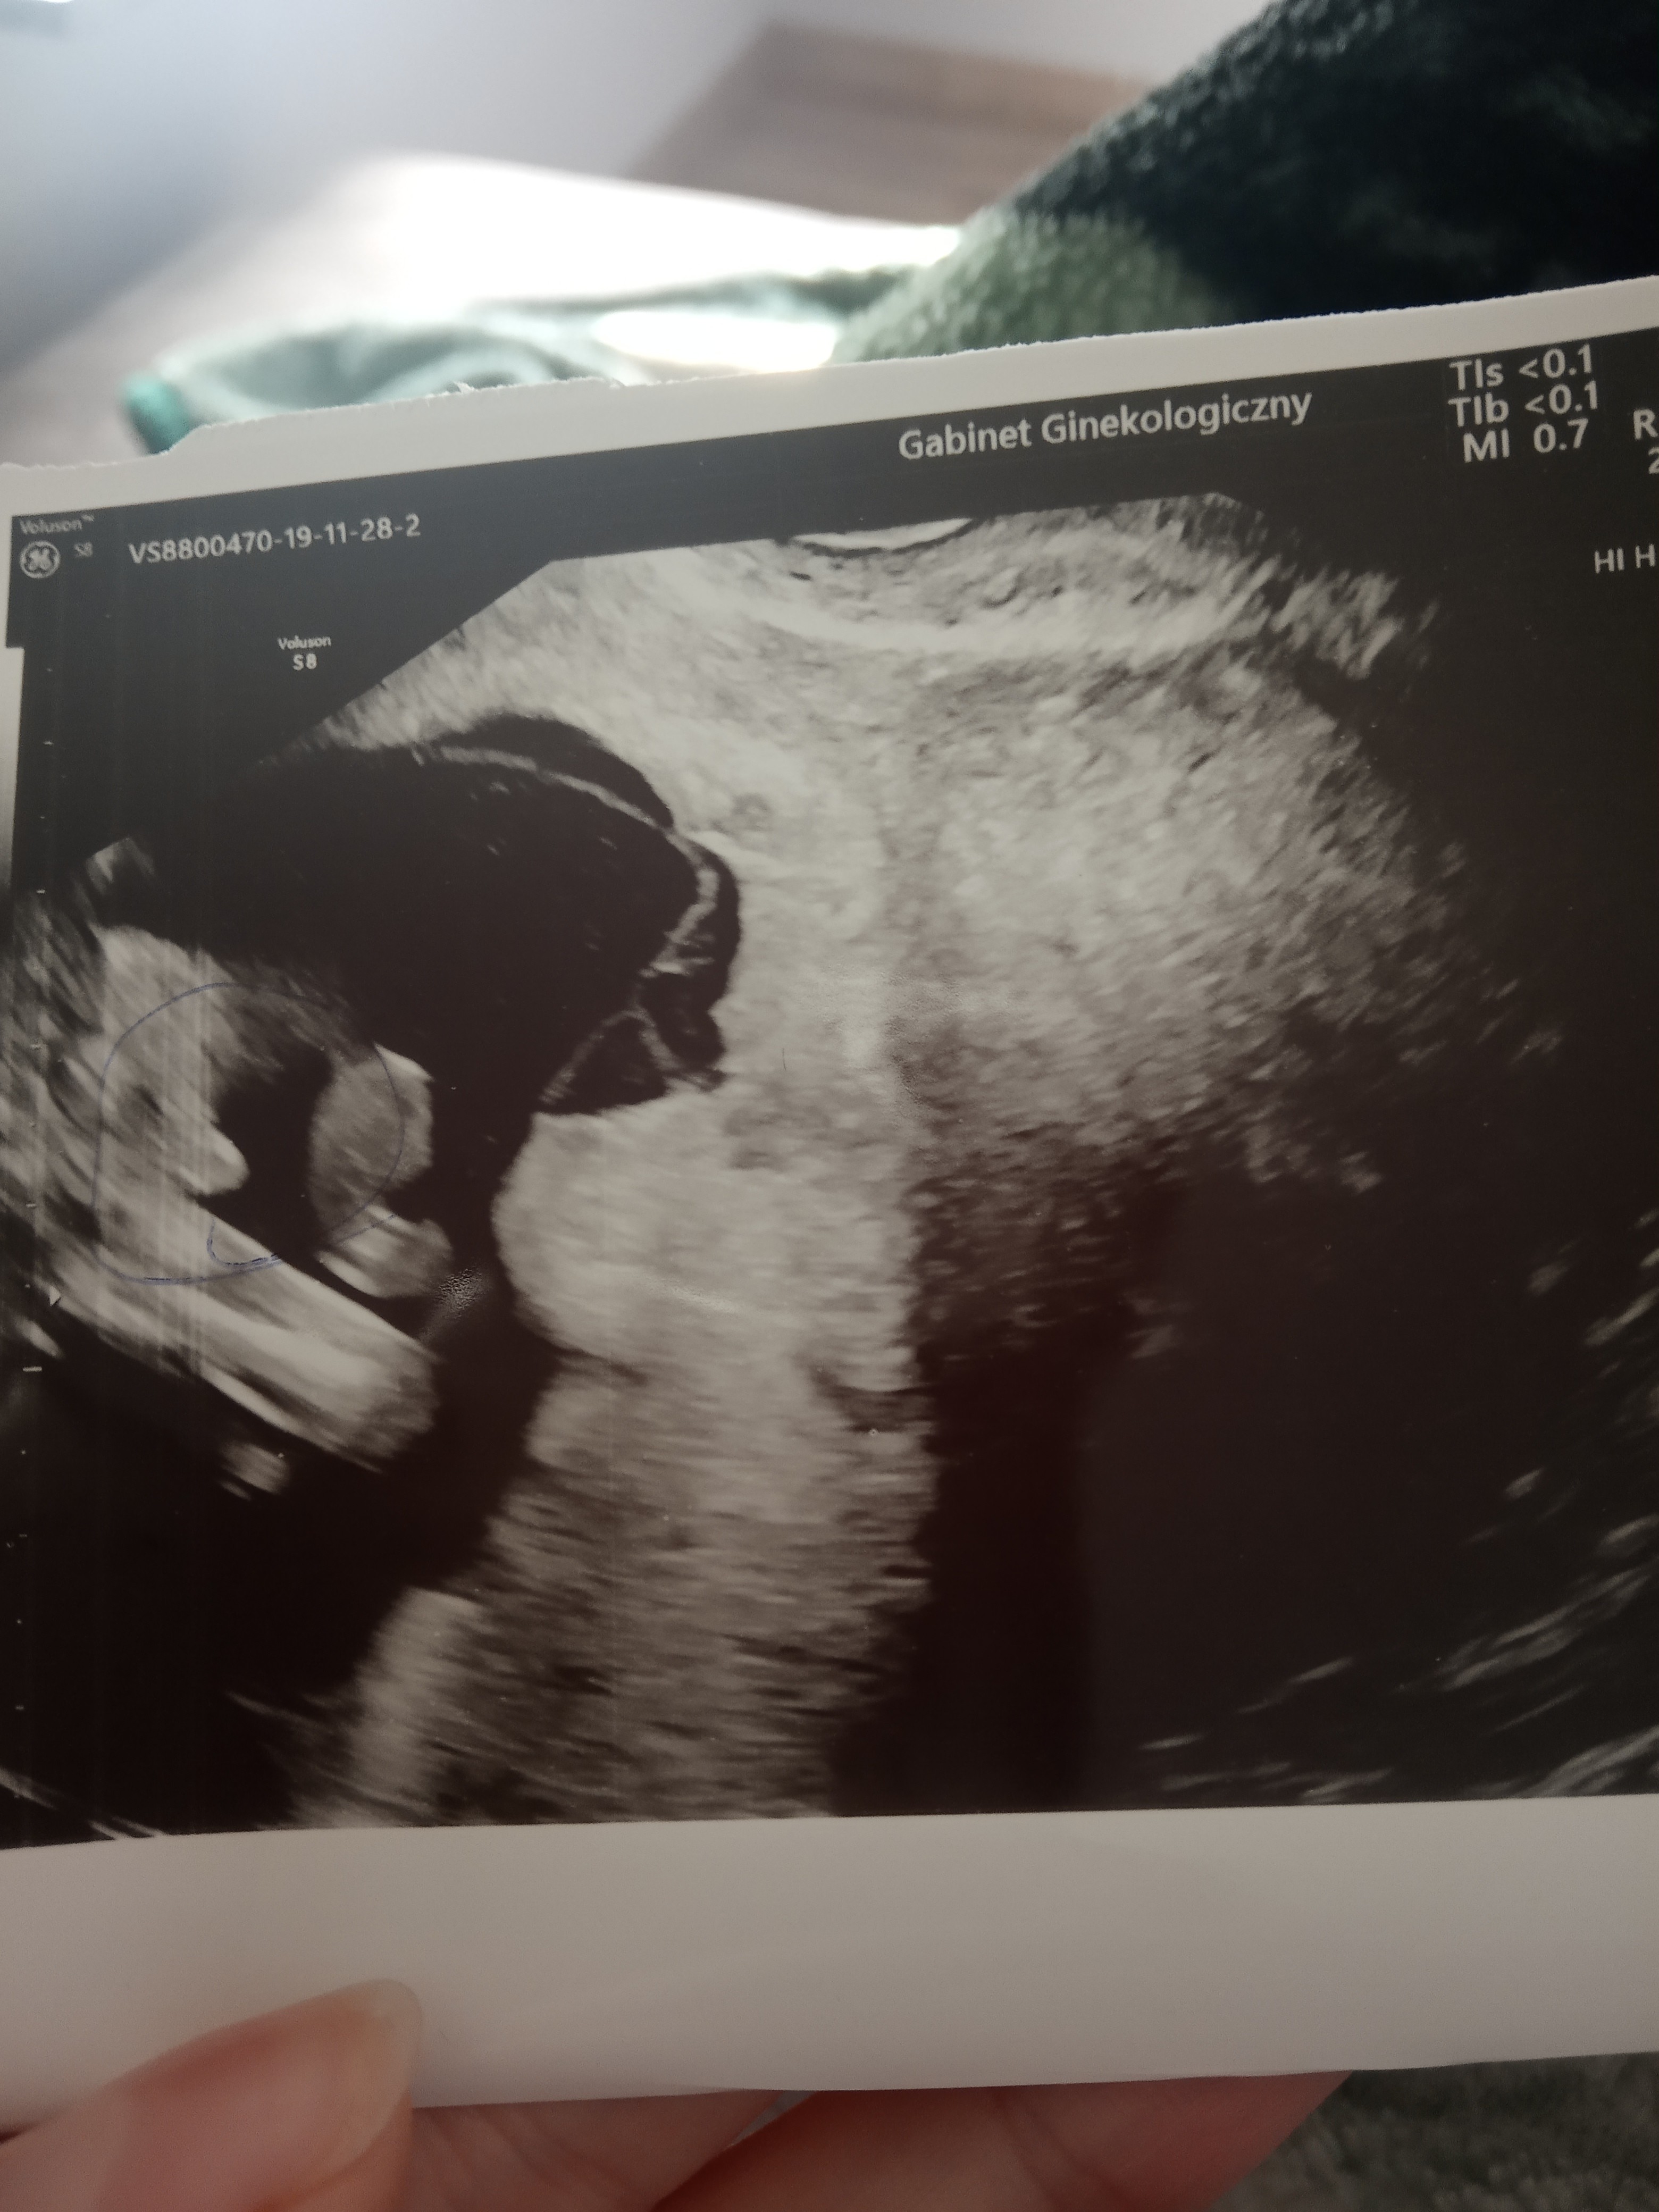

12tc. USG, chłopak czy dziewczyna?

Cześć dziewczyny, mam zdjęcia USG z 12tc+3d, podobno można stwierdzić płeć po wyrostku. Co myślicie? dziękuję za każdą odpowiedź

IMG_20191105_194815.jpg